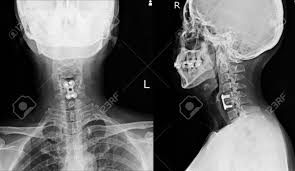

This procedure may be used to diagnose back or neck pain, fractures or broken bones, arthritis, degeneration of the disks, tumors, or other problems. Enter search terms and tap the search button. They show pictures of your internal tissues, bones, and organs. Please understand that our phone lines must be clear for urg. Here's what to expect with this painless procedure and why your dentist may recommend it.

This procedure may be used to diagnose back or neck pain, fractures or broken bones, arthritis, degeneration of the disks, tumors, or other problems. It's commonly done after someone has been in an automobile or other accident. They show pictures of your internal tissues, bones, and organs. Here's what to expect with this painless procedure and why your dentist may recommend it. Please understand that our phone lines must be clear for urg. Enter search terms and tap the search button.